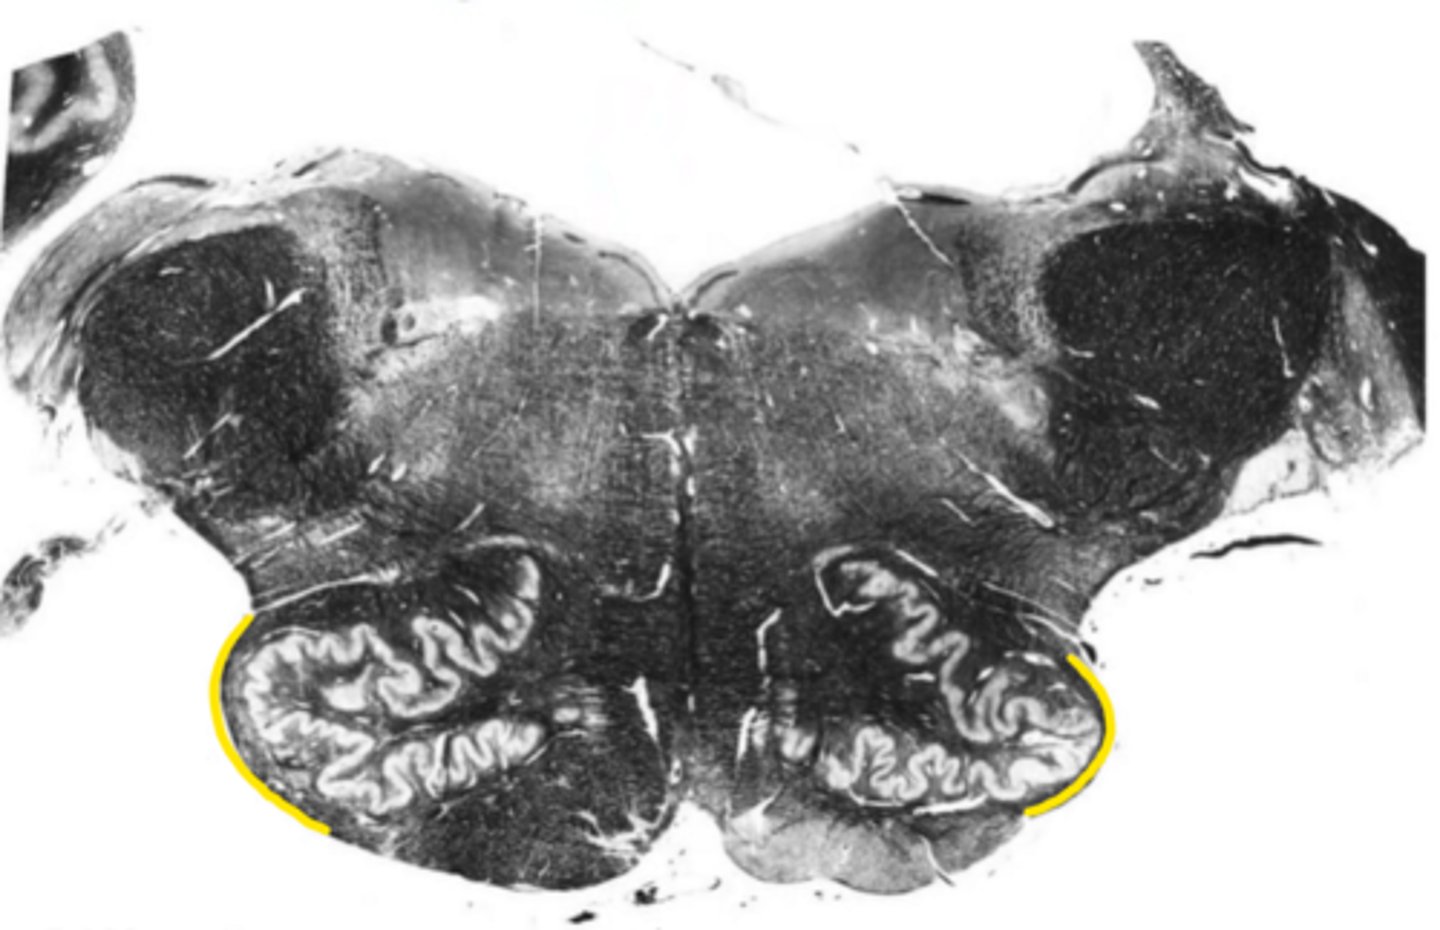

fourth ventricle

ID the space

open medulla

ID the brainstem level